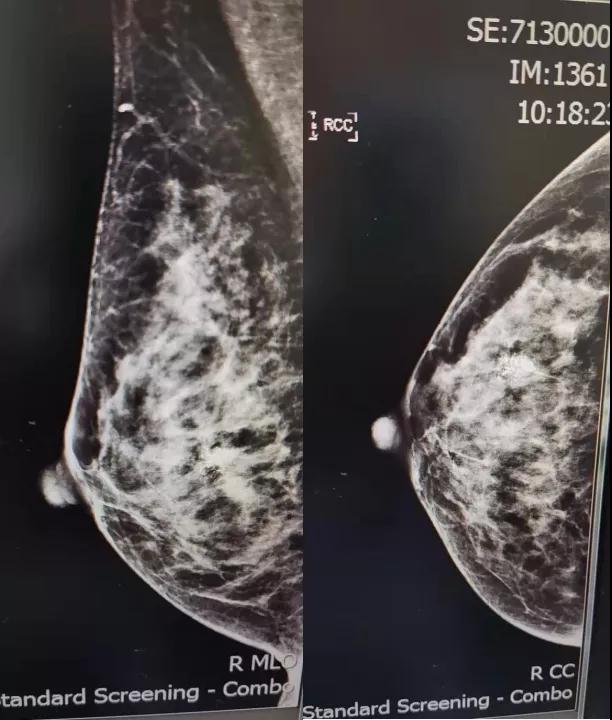

B超:右侧乳腺低回声区,大小约2. 3x1. 3cm(BI-RADS:4b类,提示:乳腺Ca不除外;

钼靶:右乳成簇钙化考虑恶性 [B1-RADS:4C类]。

MRI示: 右乳外下象限腺体边缘处肿块,考虑:乳腺癌。各项检查腋窝淋巴结均(-)。患者个人史、既往史、肿瘤家族史均无特殊。

术前钼靶

术前彩超